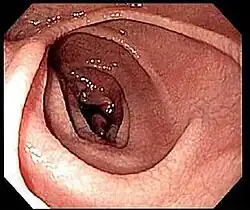

Na maior parte das pessoas com doença celíaca, o intestino delgado apresenta-se normal durante uma endoscopia. No entanto, existem cinco observações endoscópicas que sugerem doença celíaca: pregas mucosas serrilhadas, padrão em mosaico da mucosa (semelhante ao padrão de lama seca), proeminência dos vasos sanguíneos da submucosa e padrão nodular da mucosa.[67]

Até à década de 1970, as biópsias eram realizadas com cápsulas de metal ligadas a um dispositivo de sucção. A cápsula era engolida e transitava até ao intestino delgado. Após ser confirmada a sua posição através de raio X, era aplicada sucção para recolher parte da parede intestinal para o interior da cápsula. Este método foi em grande parte substituído pela endoscopia de fibra ótica, com maior sensibilidade e menor taxa de erro.[68]